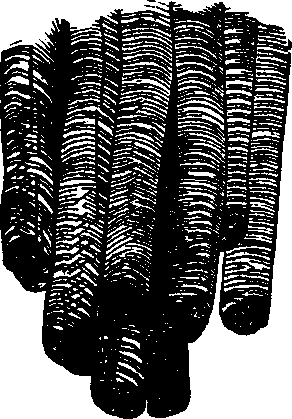

Fig. 19. Muscular fillers highly magnified.

The Muscles are those organs of the body by which motion is produced, and are commonly known as flesh. A muscle is composed of fascieuli, or bundles of fibers, parallel to one another. They are soft, varying in size, of a reddish color, and inclosed in a cellular, membranous sheath. Each fasciculus contains a number of small fibers, which, when subjected to a microscopic examination, are found to consist of fibrillæ, or little fibers; each of these fibrillæ in turn being invested with a delicate sheath. The fibers terminate in a glistening, white tendon, or hard cord, which is attached to the bone. So firmly are they united, that the bone will break before the tendon can be released. When the tendon is spread out, so as to resemble a membrane, it is called fascia. Being of various extent and thickness, it is distributed over the body, as a covering and protection for the more delicate parts, and aids also in motion, by firmly uniting the muscular fibers. The spaces between the muscles are frequently filled with fat, which gives roundness and beauty to the limbs. The muscles are of various forms; some are longitudinal, each extremity terminating in a tendon, which gives them a fusiform or spindle-shaped appearance; others are either fan-shaped, flat, or cylindrical.